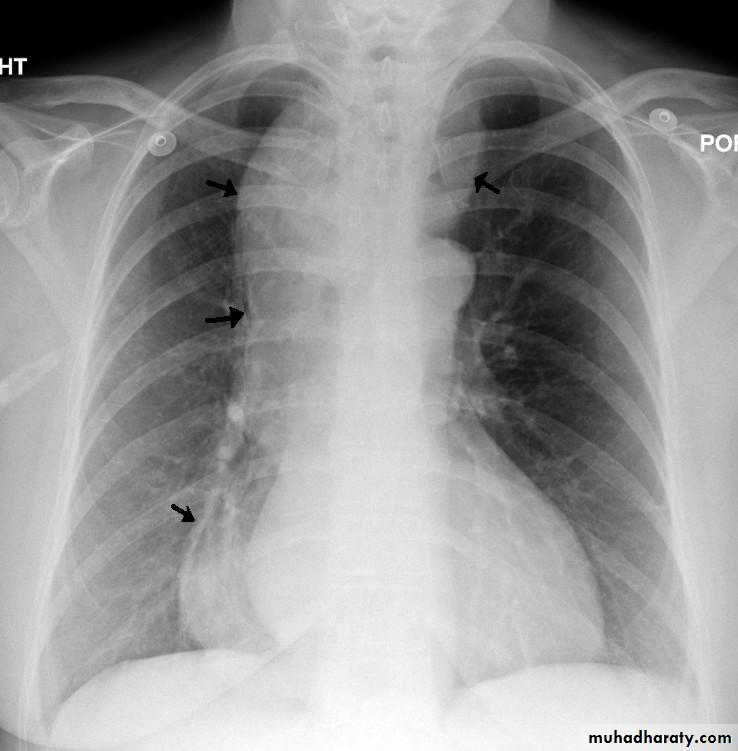

Chest x-ray may be abnormal in late dis., with widening of mediastinum (oesophageal dilatation) and presence of aspiration pneumonitis.Barium swallows . Tapered narrowing (bird beak) of the lower oesophagus and dilating body of oesophagus, a peristaltic and food filled (sigmoid oesophagus).